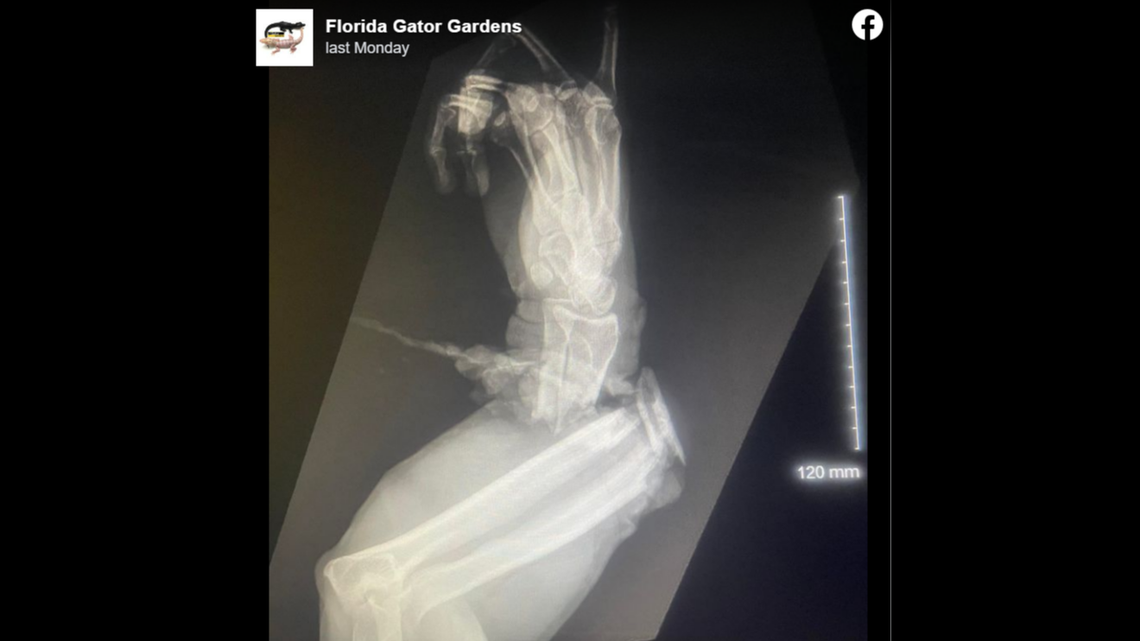

An X-ray shared by Florida Gator Gardens shows the alligator crushed the lower arm of Greg Graziani, the park’s director of wildlife. The park is in Venus, 125 miles southeast of Tampa.

Graziani was rushed to a hospital, where doctors found his hand dangling from one “tendon and some muscle that the surgeon had to untwist 6 times,” the park wrote on Facebook.

Surgery lasted nine hours, and ended with “a below the elbow amputation preserving half of his forearm,” the park said.